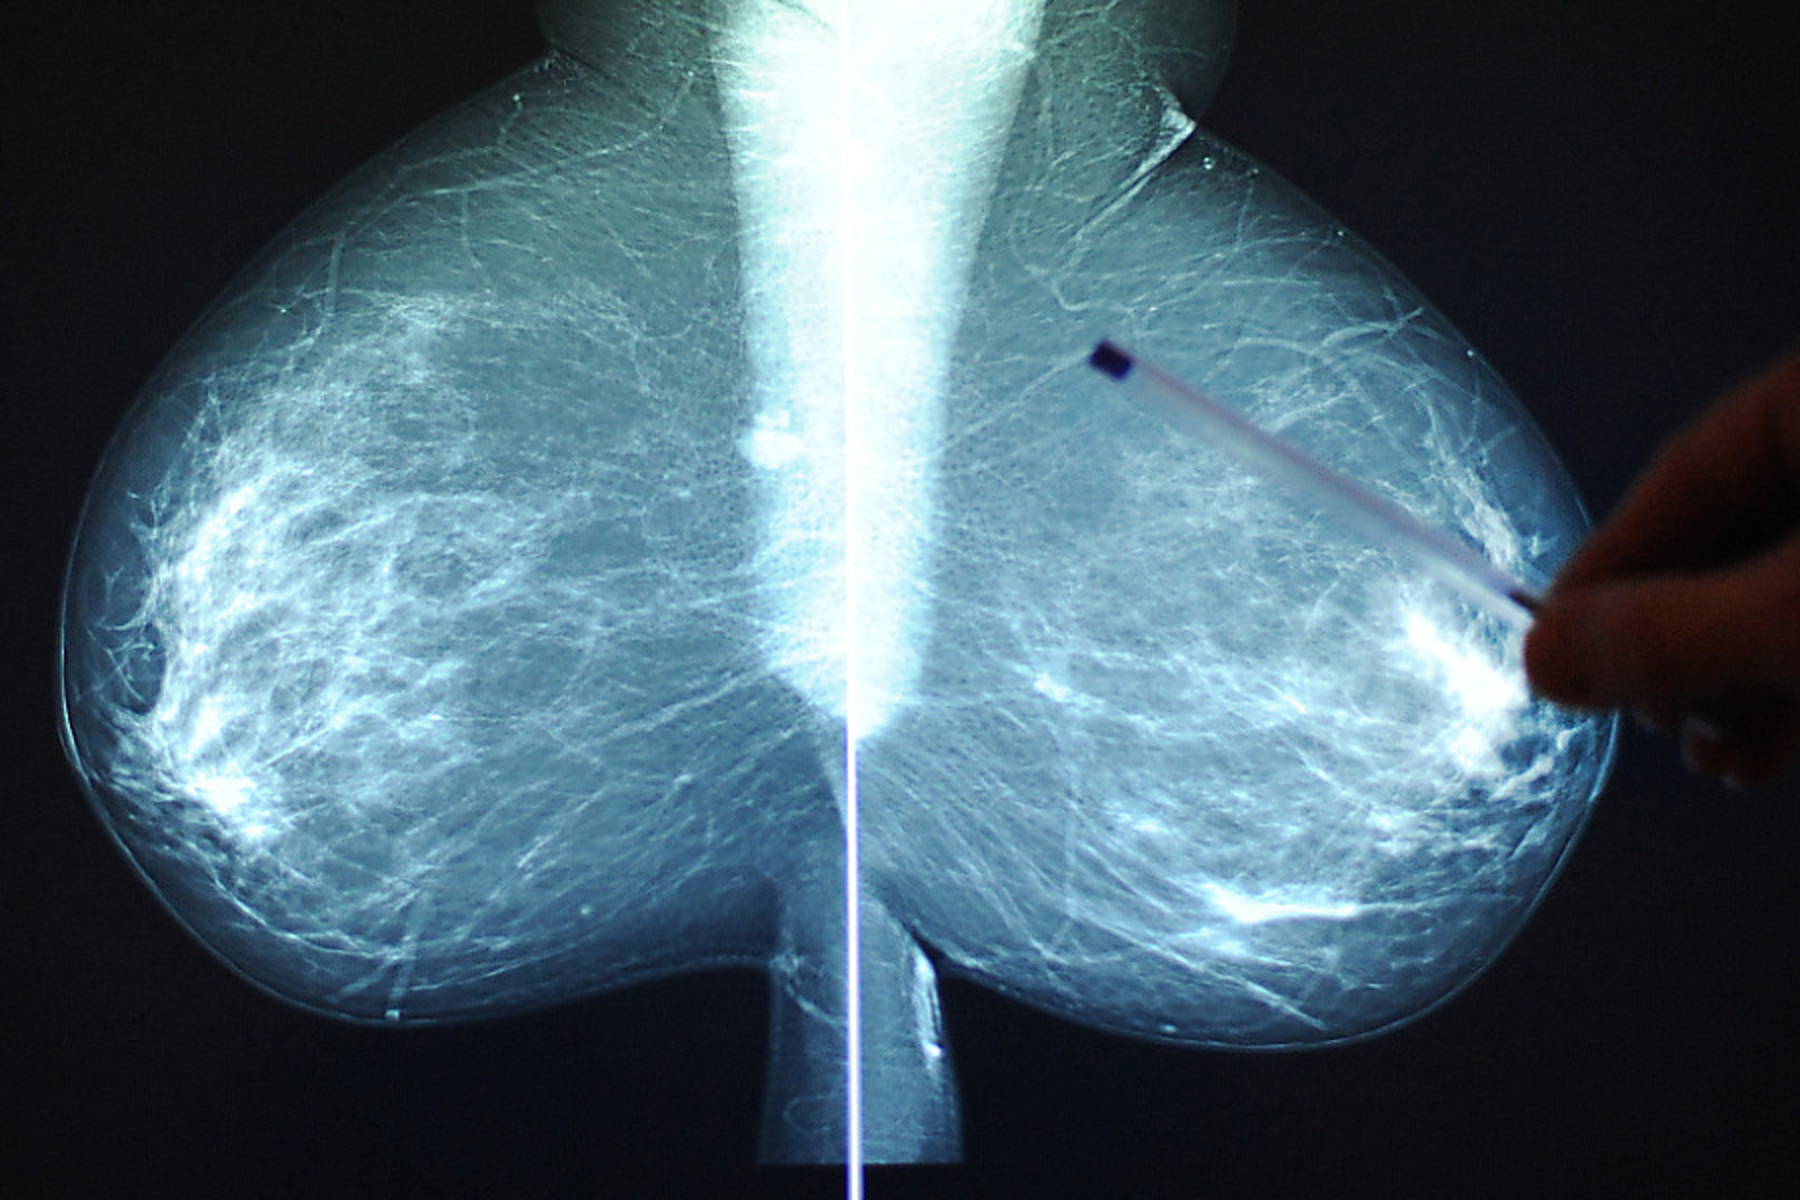

Linzer Klinik: Patientin erhielt falsche Brustkrebs-Diagnose

Die Verwechslung klärte sich noch im Gespräch mit dem Arzt auf. Das Linzer Kepler Uniklinikum bedaure den Fall und nehme ihn sehr ernst.